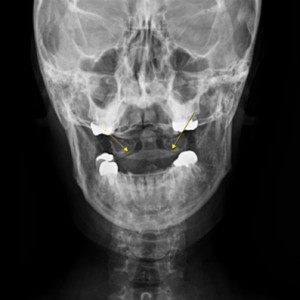

안면 두개골 엑스레이 검사

Submento Vertex View 포함

안면 두개골 CT

경추 1,2번의 변위 파악

턱관절 디스크 및 연조직 초음파

디스크 두께 파악